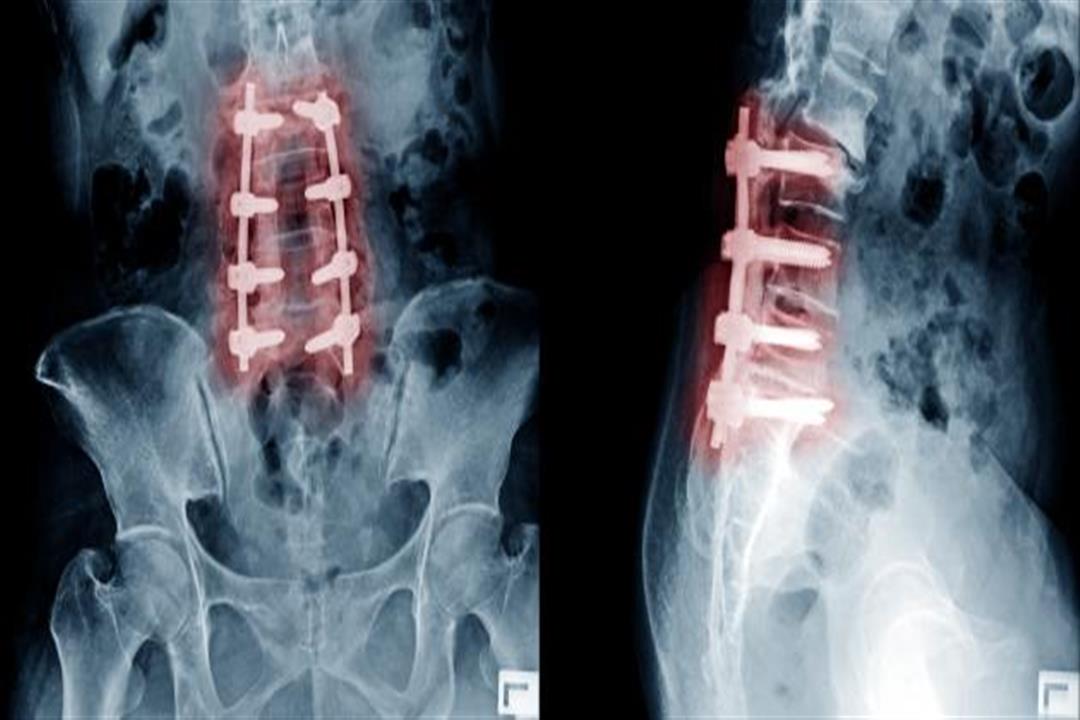

4 - كسر في الفقرات العنقية

وقد يسقط الشخص بشكل خاطئ على العنق فيتعرض لكسر في الفقرات العنقية، وفي هذه الحالة يحتاج إلى التدخل الجراحي لتثبيت الفقرات بشريحة ومسامير، ولكن في الغالب تكون عملية في منتهى الخطورة لأنها قد تستلزم الفتح بجوار النخاع الشوكي.